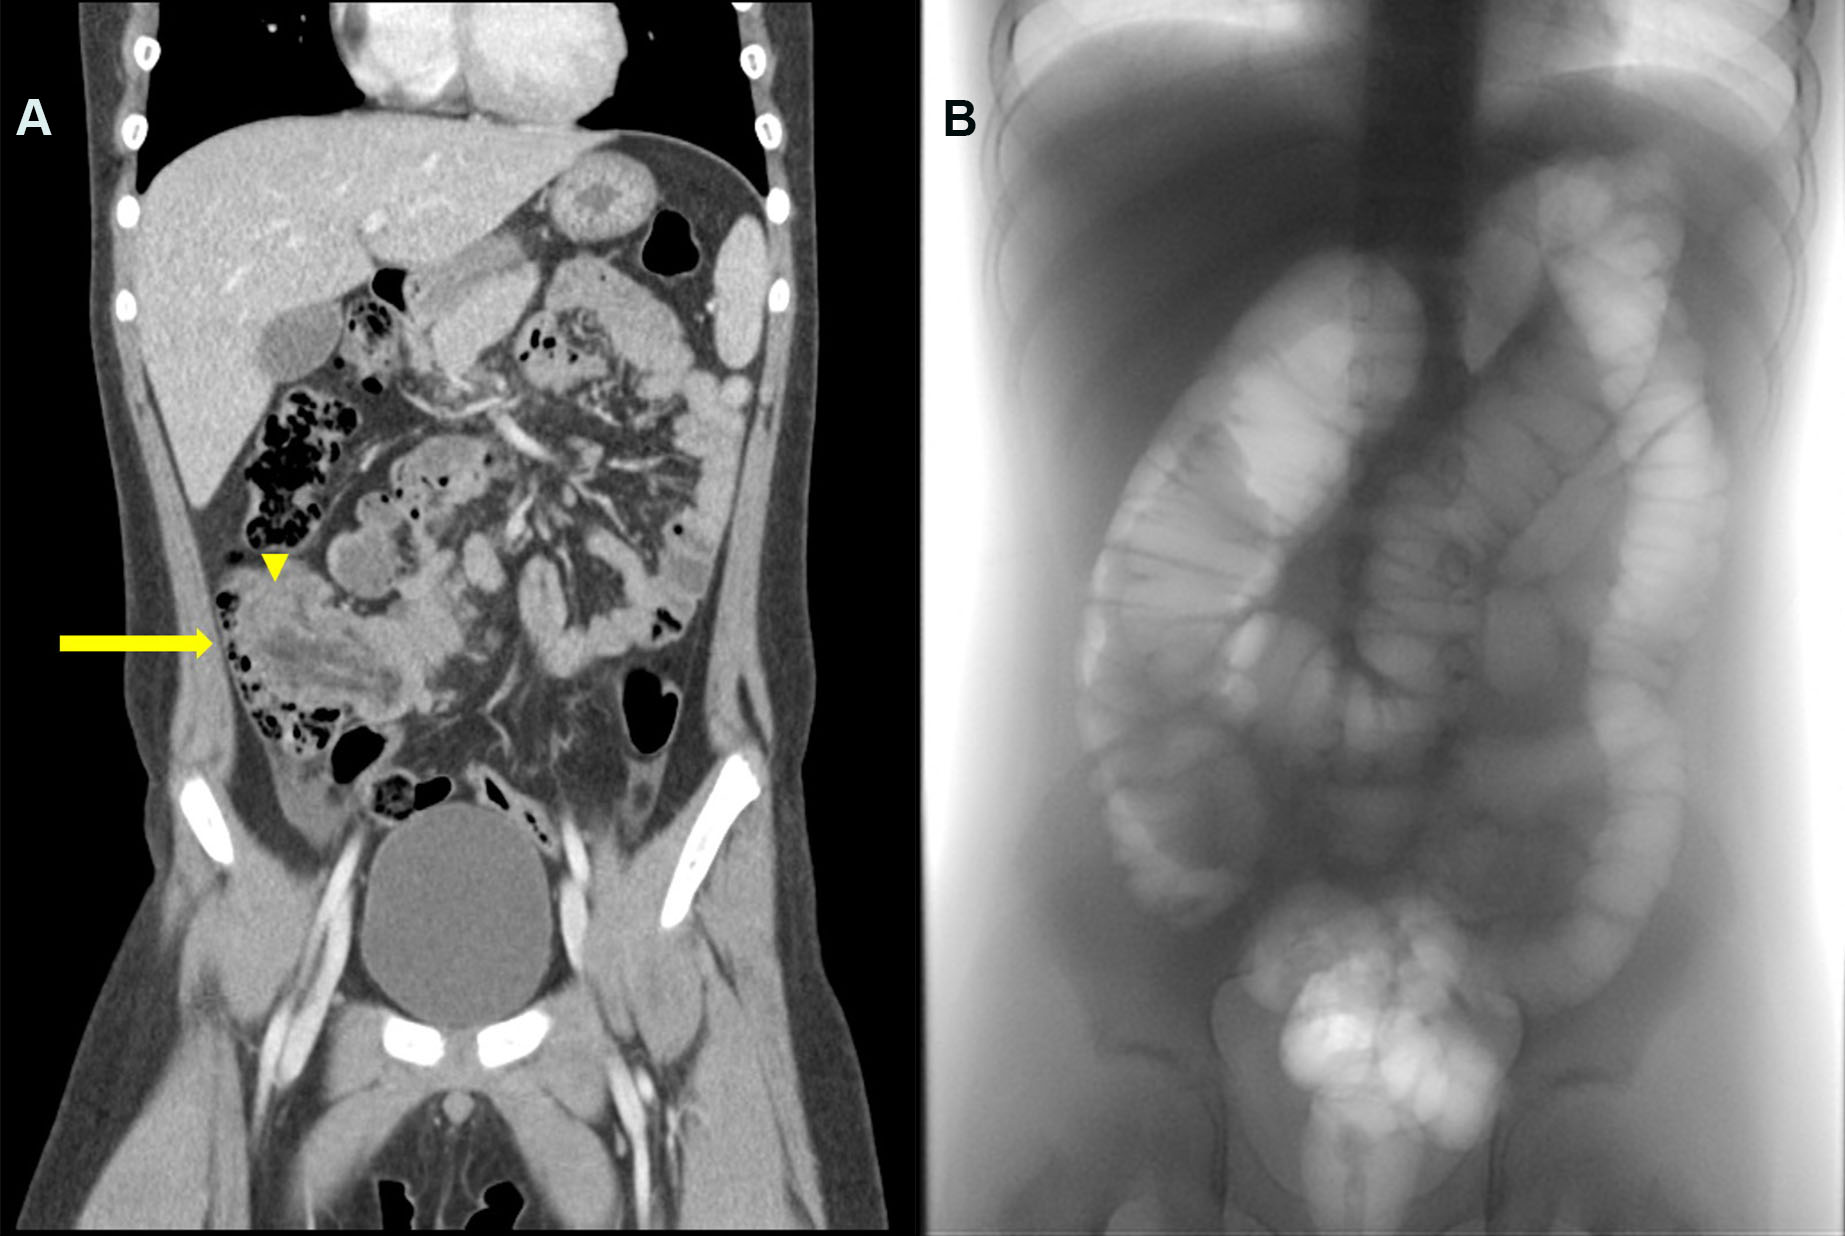

Case 1: Abdominal ultrasound and a CT scan revealed ileocecal intussusception with a suspicious lead point (Figure 1A). We then made three failed attempts at a pneumatic reduction with a maximum pressure of 130 mmHg, (Figure 1B). We performed a colonoscopy with a surgeon on standby. We noted a long intussuscepiens blocking the lumen in the hepatic flexure (Figure 2).

Figure 1

Figure 1. Initial imaging studies of Case 1. A. An abdominal CT scan revealed ileocolic intussusception (indicated by the arrow) with a pathological lead point (indicated by the arrowhead). B. Fluoroscopy showed persistent intussusception in the ascending colon after repeated pneumatic reductions.